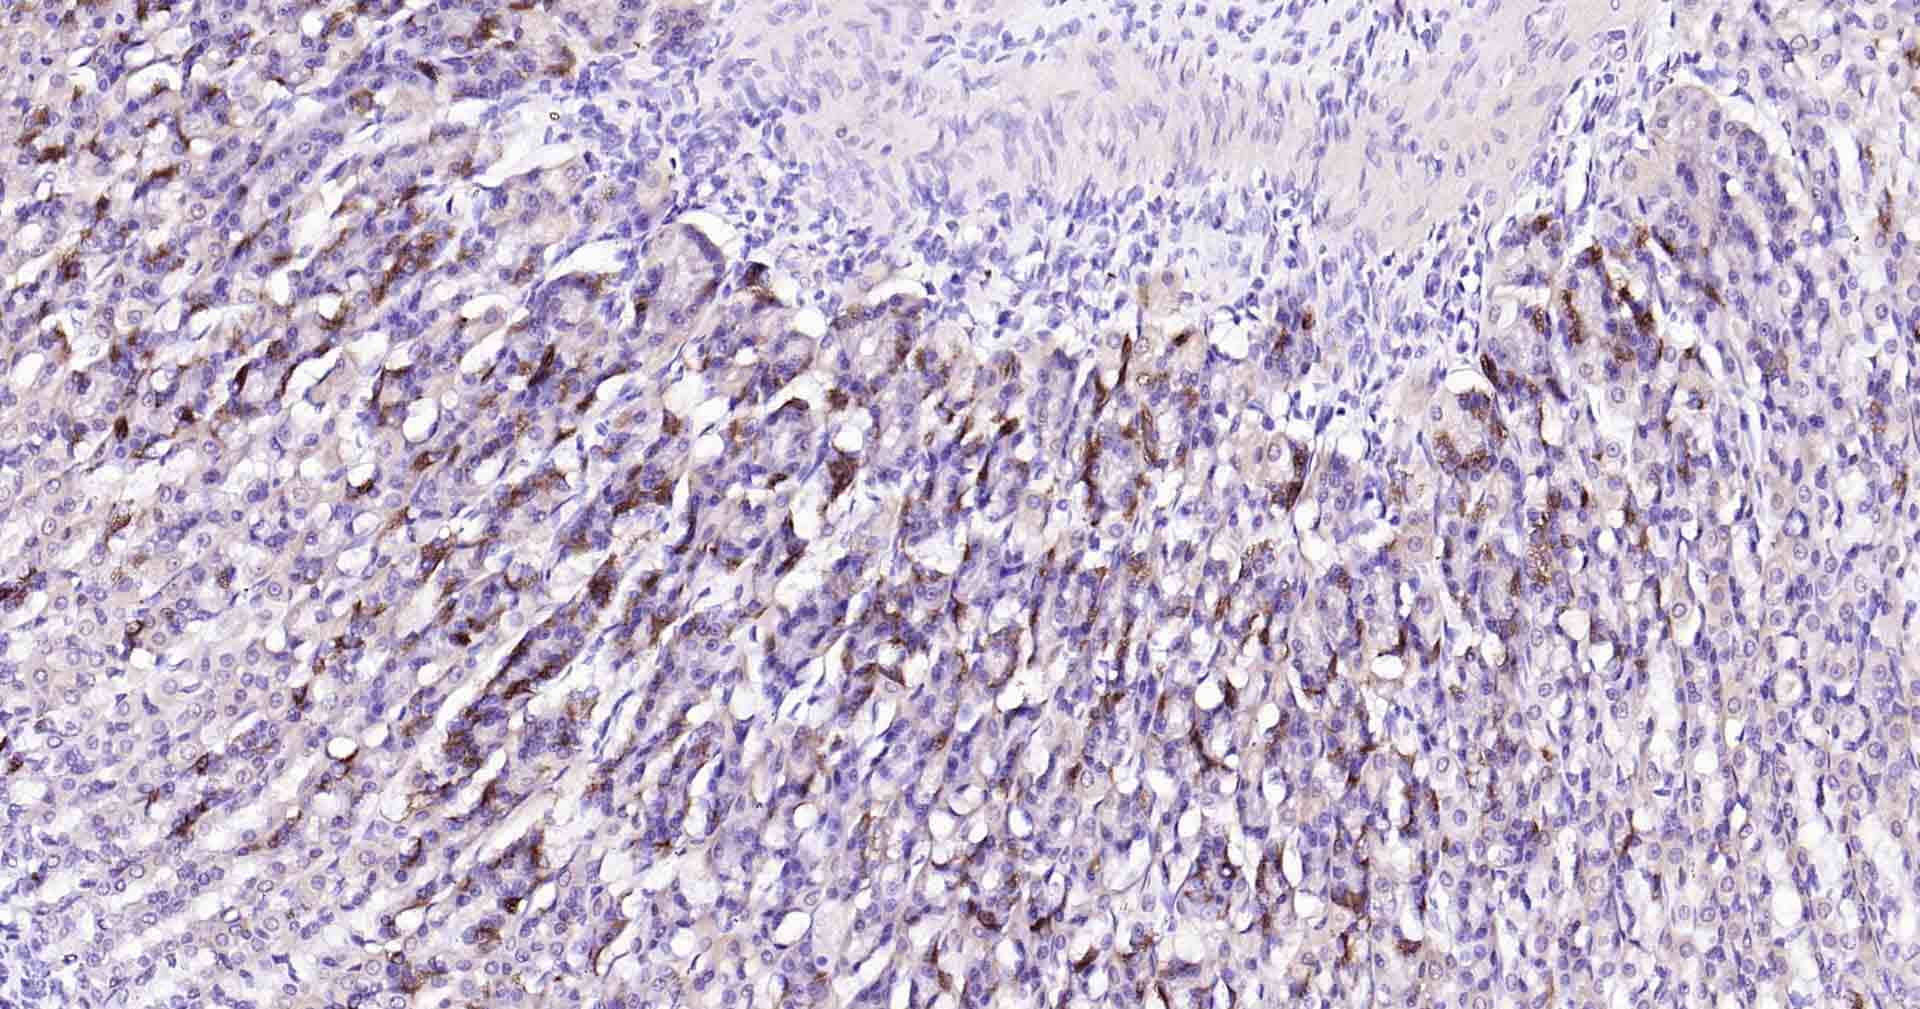

Paraformaldehyde-fixed, paraffin embedded Human Colon Cancer; Antigen retrieval by boiling in sodium citrate buffer (pH6.0) for 15 min; Antibody incubation with Beclin 1 Monoclonal Antibody, Unconjugated(bsm-41365R) at 1:50 overnight at 4°C, followed by conjugation to the SP Kit (Rabbit, SP-0023) and DAB (C-0010) staining.